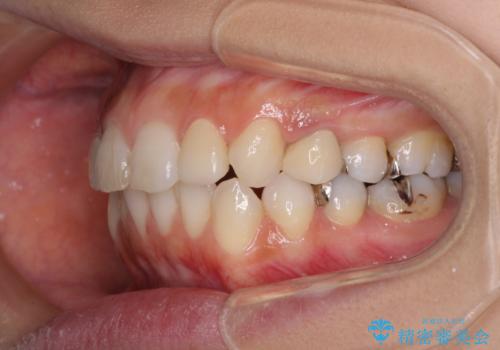

複数歯の補綴治療を行う場合、仮歯やセラミッククラウンを装着する度に保定装置を作り替える必要があり、その度に後戻りを起こす可能性が高くなります。

インビザラインであれば、矯正治療後半で補綴治療を行い、その後矯正治療を継続することでスムーズに治療を終えることができます。